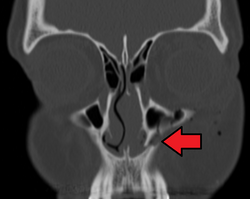

The maxillary sinus appears as a shallow groove on the nasal surface of the bone about the fourth month of development, but does not reach its full size until after the second dentition.

The maxillary sinus presents the appearance of a furrow on the lateral wall of the nose. In the adult the vertical diameter is the greatest, owing to the development of the alveolar process and the increase in size of the sinus.